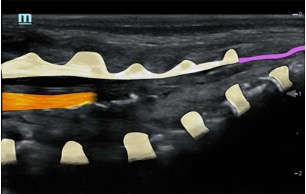

- It helps in identifying spinal dysraphism (contraindication for the block; see image library)

- It aids in identifying the correct location for needle insertion and will subsequently confirm the needle tip position when injecting

- It visualises the caudal sac and thus will prevent intrathecal injection.

- Utilising saline for the initial injection reduces the likelihood of intravascular administration of local anaesthetic, thereby minimising the risk of local anaesthetic toxicity.

- It allows you to follow the spread of the local anaesthetic and confirm the level of the block.

1)Probe position transverse over the sacral cornua (-> frog’s eyes US view)

2)Then rotate probe 90 degrees for a longitudinal view

Identify:

•Sacral cornua

•Sacrum

•Sacrococcygeal membrane

•End of the dural sac (hyperechoic (<-> CSF are anechoic (black)

•Caudal epidural space

•Assess the position of the dural sac in relation to the sacrococcygeal membrane

Perform saline test à Confirm position (saline expands the epidural space and pushes the dura more anteriorly)

Track the LA spread by sliding the probe cranially (probe positioned paramedian longitudinally); ensure the appropriate level is reached for the intended operation